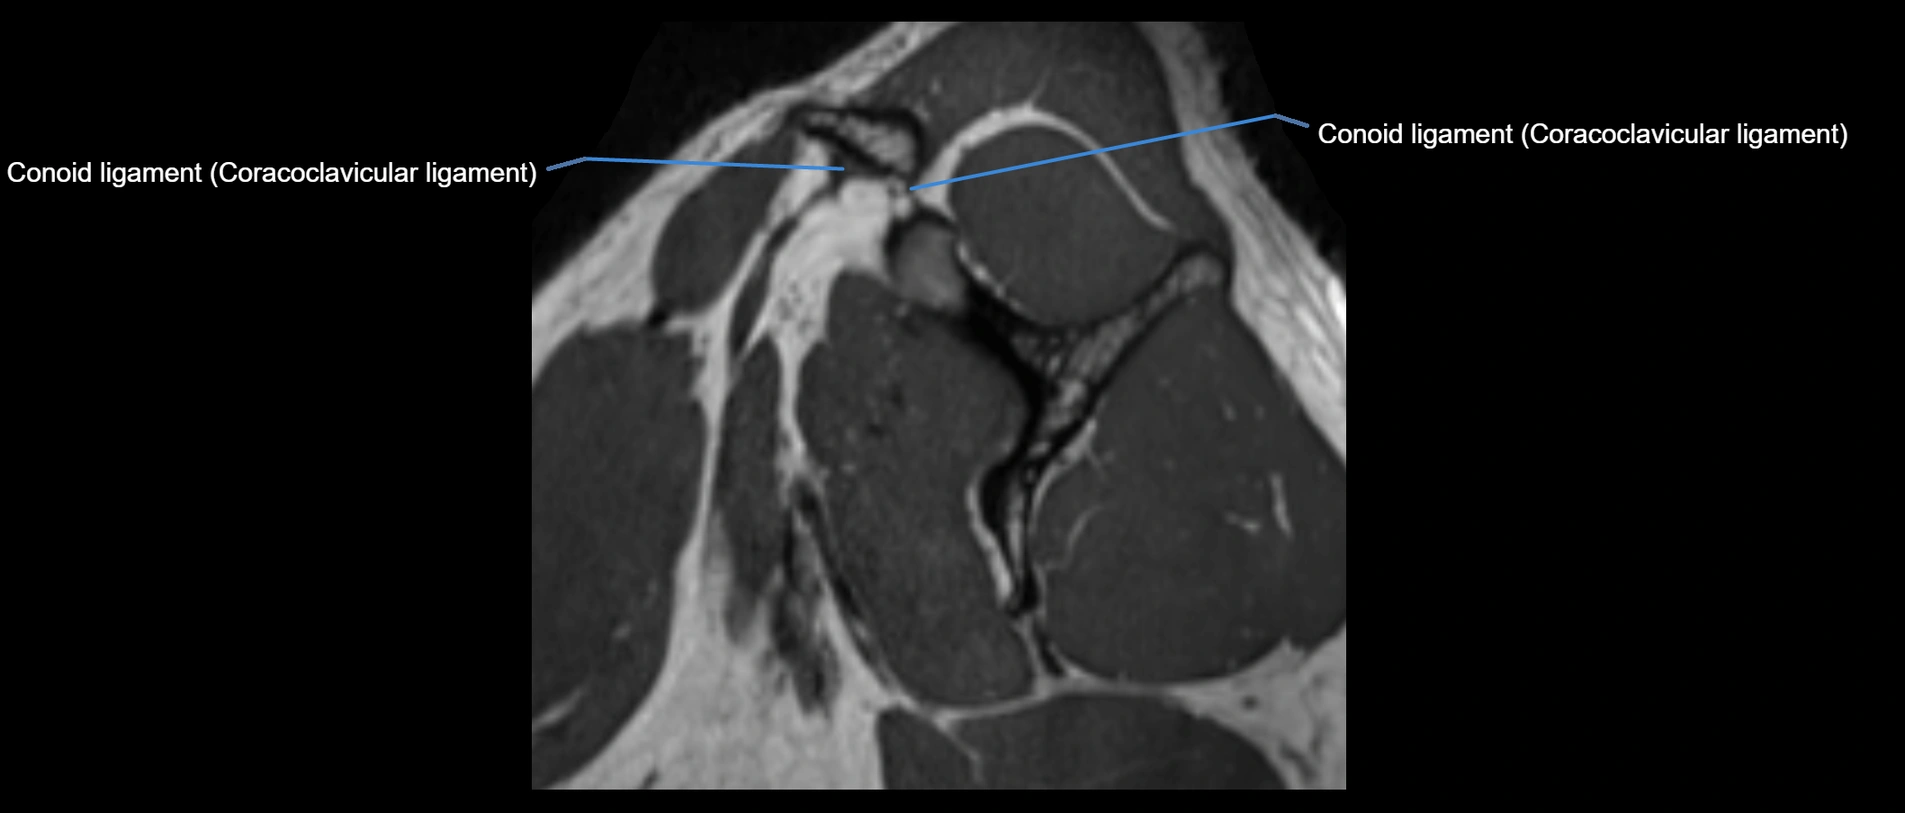

CT image

image